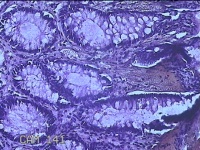

性别

男

年龄

40岁

临床诊断

混合痔

一般病史

反复肛门肿物突出15年。

标本名称

肛门肿物

大体所见

灰白暗红色肿物0.7x0.5x0.2cm一个,表面糜烂。

脱水、透明,浸蜡、脱蜡效果不佳,制片质量差。